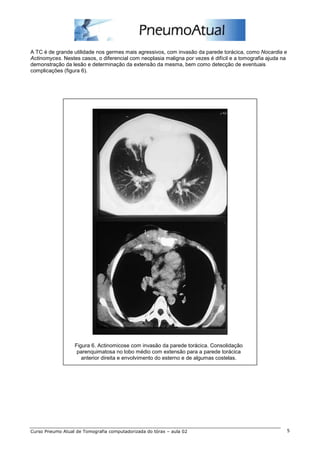

A TC é de grande utilidade nos germes mais agressivos, com invasão da parede torácica, como Nocardia e

Actinomyces. Nestes casos, o diferencial com neoplasia maligna por vezes é difícil e a tomografia ajuda na

demonstração da lesão e determinação da extensão da mesma, bem como detecção de eventuais

complicações (figura 6).

Figura 6. Actinomicose com invasão da parede torácica. Consolidação

parenquimatosa no lobo médio com extensão para a parede torácica

anterior direita e envolvimento do esterno e de algumas costelas.